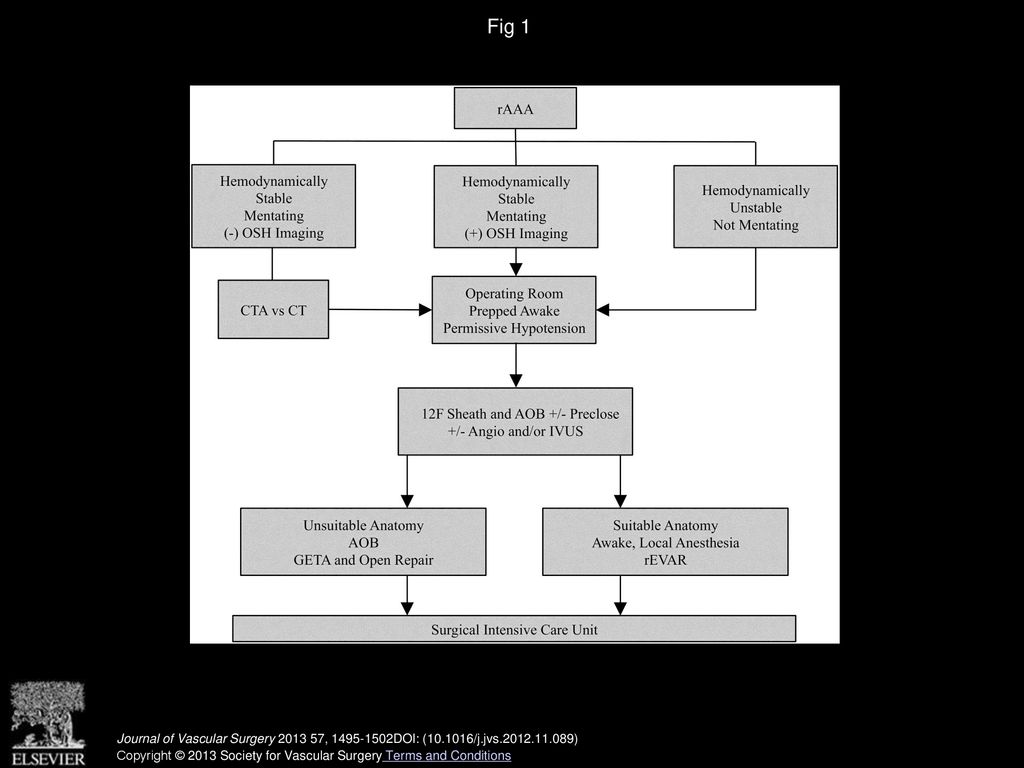

PC068 Local Anesthesia Based Endovascular Repair Of Ruptured Abdominal

PC068 Local Anesthesia Based Endovascular Repair Of Ruptured Abdominal